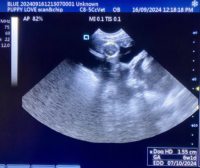

Mobile Ultrasound Pregnancy Scanning and Microchipping Services

Puppy Love scan and chip